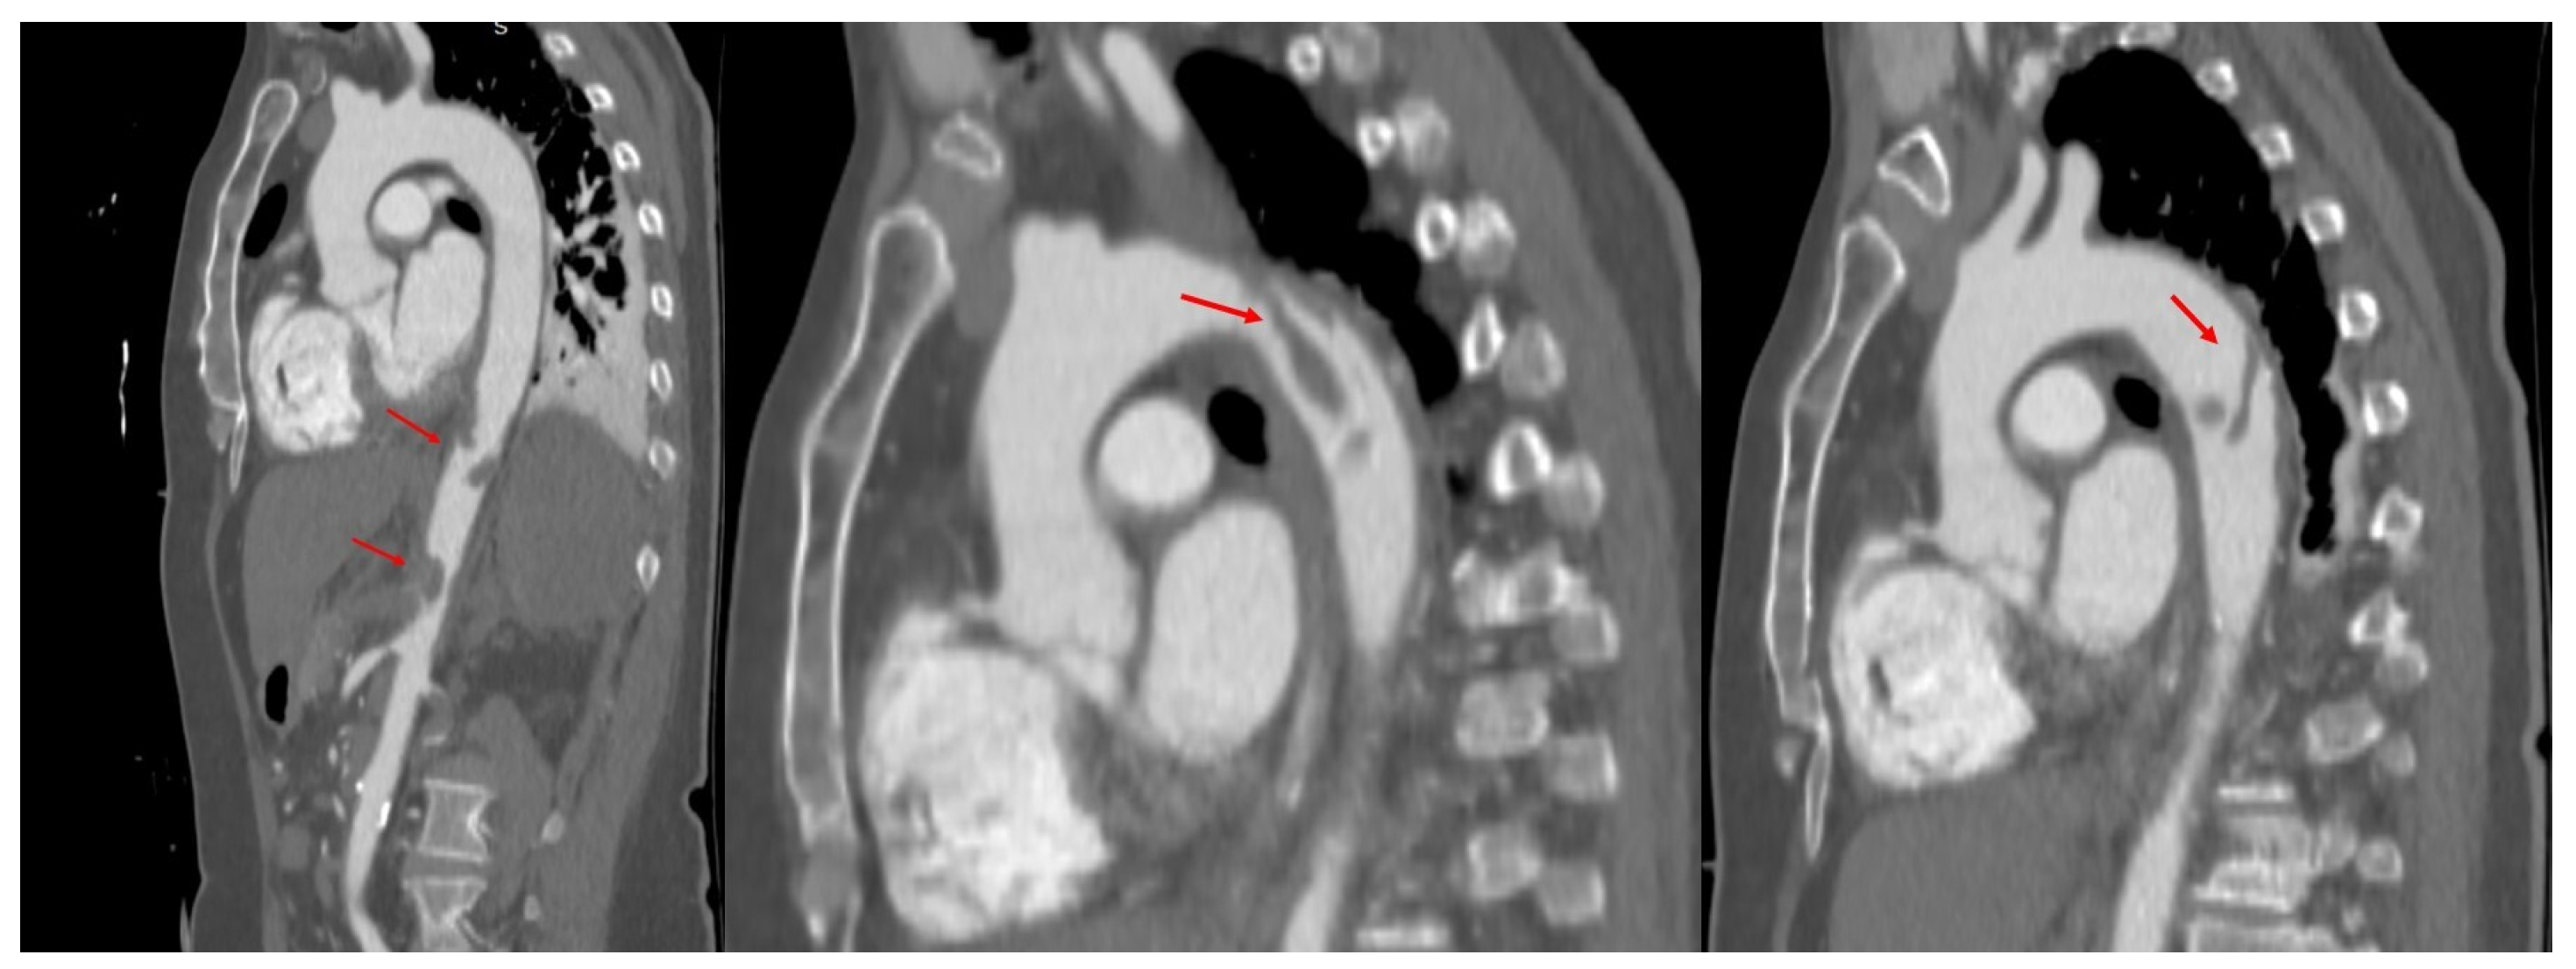

2. Case Presentation